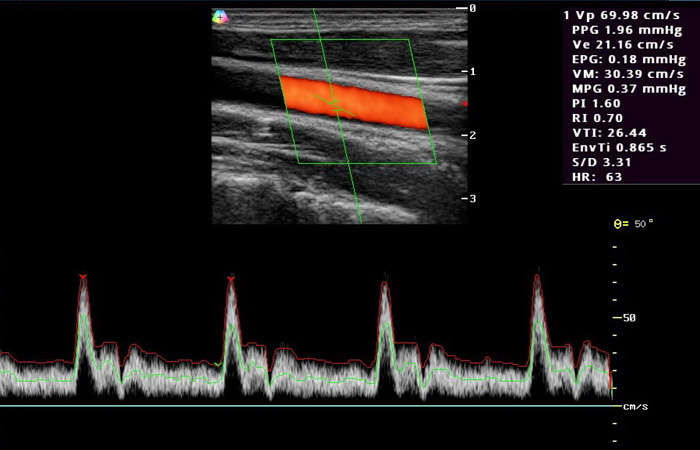

Το έγχρωμο Doppler υπερηχογράφημα ή triplex αγγείων είναι η μέθοδος με την οποία ελέγχουμε σε πραγματικό χρόνο την ροή του αίματος μέσα στα αγγεία του σώματος (π.χ. καρωτίδες, σπονδυλικές αρτηρίες, κοιλιακή αορτή, λαγόνιες αρτηρίες και φλέβες, φλέβες και οι αρτηρίες των άνω και κάτω άκρων) με τρόπο μη επεμβατικό, γρήγορο και ανώδυνο. Συγκεκριμένα, μας παρέχει πληροφορίες για την ανατομία των αγγείων, την τυχόν ύπαρξη αθηρωματικών πλακών ή στενώσεων στον αυλό των αρτηριών, την ύπαρξη και τον βαθμό επικινδυνότητας τυχόν ανευρύσματος της κοιλιακής αορτής, καθώς και για παθολογικές καταστάσεις των φλεβών ( θρόμβωση, βαλβιδική ανεπάρκεια).

Επίσης με τη χρήση του triplex είναι δυνατή η εκτίμηση της αγγείωσης του παρεγχύματος των διαφόρων οργάνων του σώματος, καθώς και η ανάδειξη της αιμάτωσης παθολογικών εξεργασιών.